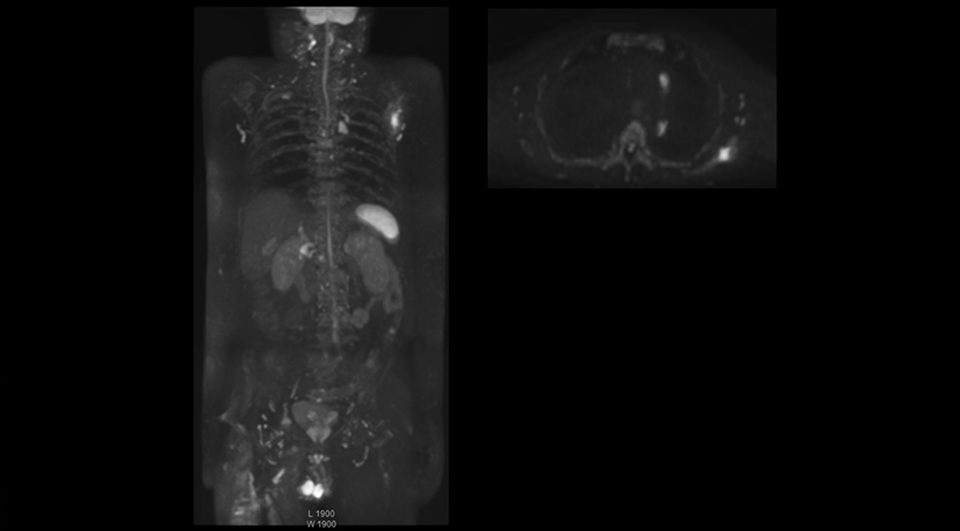

“The DWIBS sequence’s value in oncology cases is due to the high contrast it creates between lesions and surrounding tissue. Whole body DWI is requested by physicians who need to clarify TNM staging or determine therapeutic strategies, oncologists in need of diagnosis or follow-up scans, surgeons who need to see the presence of distant lesions that are sometimes difficult to detect by CT before surgery, and urologists for the evaluation of bone lesions, and the effect of chemotherapy and radiotherapy.”

“mDIXON FFE allows us to quickly get information we need to assess the presence of fat. That gives us more information when we need to diagnose bone lesions, and when we are asked to judge fat-containing lesions such as hepatocellular or renal carcinoma,” Dr. Nobusawa says. “The mDIXON fat images can help us to differentiate fatty bone marrow from bone lesions. This is especially useful in elderly people, who tend to have fattier bone marrow. The water images provide a high signal-to-noise ratio in the intestinal canal, which is valuable for visualizing lesions in the colon,” he says.

“In-phase and out-phase sagittal T1-weighted FFE images help us to visualize and further characterize bone lesions such as metastasis and bone-marrow hyperplasia that have high signal on DWI. These images are also used throughout radiotherapy, to monitor changes in the fatty bone marrow.”

After implementing the improved whole body protocol, the radiology team initially did not see a large increase in referrals, although Dr. Nobusawa saw clinical cases where the DWIBS images provided him valuable information for diagnosis. This is why Dr. Nobusawa and Mr. Naka started to actively educate referring physicians about the value of whole body DWIBS. They organized several presentations for physicians in the hospital, where they explained how DWIBS can be of value in oncology patients. The information it provides can be useful for physicians when staging cancer, as well as when determining or adjusting treatment strategy. Mr. Naka remembers some cases where DWIBS provided remarkable information. “In one example, DWIBS visualized bone lesions that could not be seen on PET or SPECT. In another case we had found a bone lesion when a normal L-spine scan for narrowing of the disk space was done. One extra DWIBS scan (2 stations, 8 minutes) demonstrated a lesion that later was confirmed to be the primary region of cancer.”